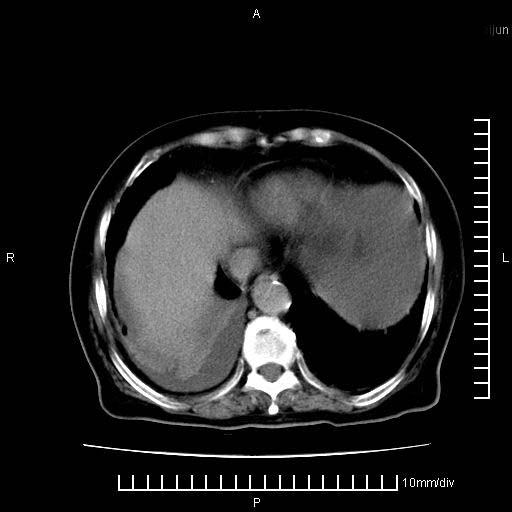

标题: CT28280:腹部增强:女性,80岁

上腹疼痛月余,外院核磁诊断胰腺癌。现临床示右下腹可明显触及包块,可片子上怎么没有看到?

1.胰腺颈体部癌。

2。腹腔积液。

3。右胸腔积液,伴右肺下叶部分萎陷。

4。右肾盂囊肿。

胰腺体部癌累及周围器官,腹膜、粘连

1。胰腺ca伴腹膜腔转移

2。肝左叶低密度灶,考虑转移可能

胰腺结构模糊,胰尾部见囊性包块,周围脂肪密度增高,左肾前筋膜增厚,胸水、腹水。不符合胰腺ca伴腹膜腔转移。考虑胰腺炎伴假性囊肿形成、胸腹腔积液。

右肾盂囊肿。